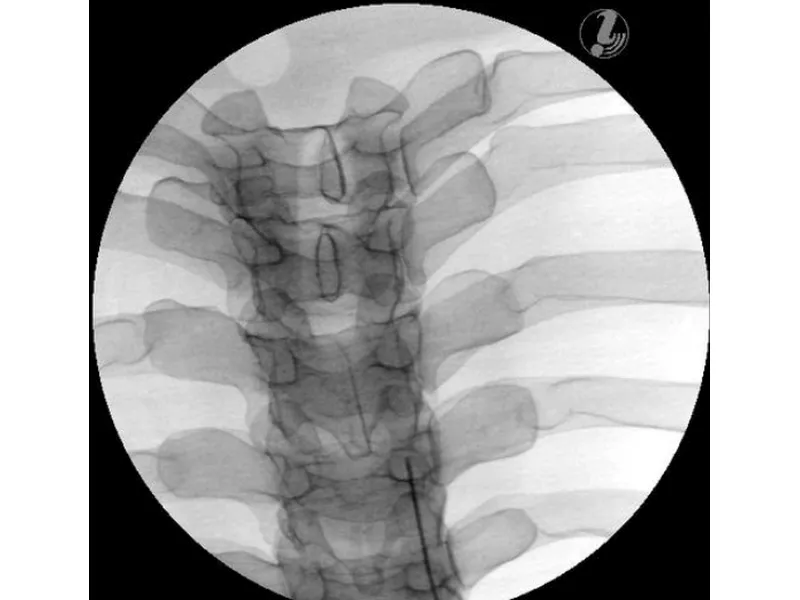

Манекен для инъекций имеет анатомически точную костную структуру (позвонки T3-T8, ребра 3-8) и реалистичную тактильную обратную связь в ходе практики. Кроме того, он выполнен из самовосстанавливающегося материала, который позволяет многократно использовать тренажер.

- Интерламинарная эпидуральная инъекция стероидов

- Трансфораминальная инъекция в грудной отдел

- Дугоотростчатый сустав грудного отдела позвоночника

- Инъекция в нерв (медиальную ветвь)

- Внутрисуставная инъекция

- Блокада межреберных нервов (ICNB)